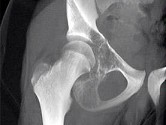

- 单项选择题如图所示,患儿的最可能的诊断是 ( )

A、骨髓炎

B、尤文肉瘤

C、骨肉瘤

D、软骨肉瘤

E、以上都不是